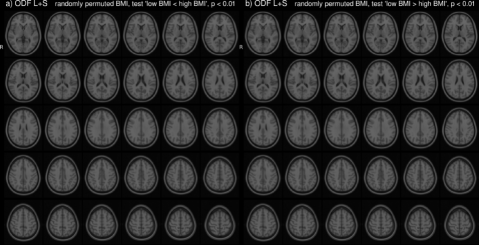

In the HCP dataset, ODFs correlate strongly with the demographic variable BMI. As expected, the ODFs negatively correlate (Fig. 7b) with BMI, indicating a loss of anisotropy with increasing BMI (Fig. 5a,b). This result is consistent with the well-established negative association between global white matter integrity and physical obesity (Mueller et al., 2011; Stanek et al., 2011; Verstynen et al., 2012; Gianaros et al., 2013; Verstynen et al., 2013). The fiber directions (Fig. 8a,b) identified from can be used to perform tractography (Fig. 8c,d). Resulting tracts (Fig. 8c,d) show a pronounced loss of anisotropy in the corticospinal tracts, the optic radiations and the right superior longitudinal fasciculus. These results are corroborated by the existing methods TBSS (Fig. 9a,b, S2a,b), Connectivity-based fixel enhancement (Fig. 9c,d, S2c,d) and local connectometry (Fig. 9e,f, S3a,b). The volume of positive findings of correlation with BMI is largest when using the full ODF information with the ODF approach (Fig. 9). In addition, in a test of specificity, no voxels are found to correlate with randomly permuted BMI (Fig. S4).

The individual variability of ODFs can be caused by ODF reconstruction errors due to image artifacts (Fig. S5.1), registration errors and individual differences in brain structure (Fig. S5.3-4). In the HCP ODFs individual variability due to the first two of these contributions is limited by the low number of artifacts and the high image resolution in the HCP DWI images. As a result, ODF correlations of BMI identified with ODF ((Fig. 9g,h, S3c,d)) and ODF (Fig. 9i,j, 7) are similar in this dataset. However, in a dataset with higher individual variation, notable improvement of ODF over ODF PCA can be observed (Baete et al., 2016a).